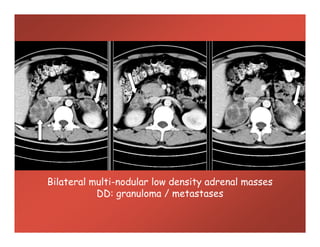

Bilateral multi-nodular low density adrenal masses

DD: granuloma / metastases